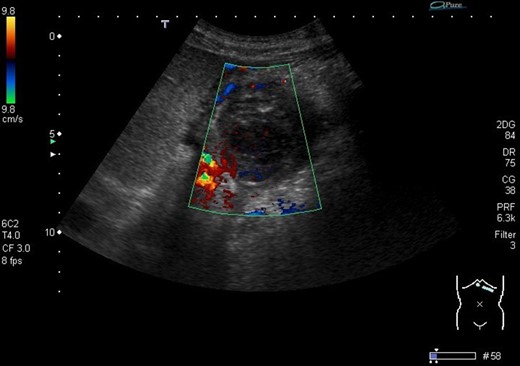

The next step was an endoscopic ultrasound guided thrombin injection. This was carried out and 2 ml of thrombin was injected into the pseudoaneurysm to good effect with no immediate complications. Also, percutaneous drainage of the perisplenic collection was carried out, where 400 ml of pus was drained. A follow-up duplex ultrasound scan confirmed that there was no flow in the pseudoaneurysm (Fig. 3).

Ultrasound image demonstrates the thrombosed pseudoaneurysm 24 h post thrombin injection.